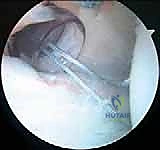

3. الاستكشاف التشخيصي بالمنظار:

قبل البدء بالإصلاح، يقوم الجراح بجولة استكشافية شاملة داخل المفصل. يتم تقييم الشفة الأمامية، الخلفية، العلوية، الغضاريف المفصلية، وأوتار الكفة المدورة للتأكد من عدم وجود إصابات مصاحبة خفية.

4. تحضير موقع الإصلاح (Preparation):

يتم استخدام أدوات دقيقة لتنظيف الأنسجة التالفة وإزالة أي ندبات. الخطوة الأهم هي "تخشين" (Abrasion) حافة عظم التجويف الحقاني الخلفي. هذا التخشين يهدف إلى إحداث نزيف دقيق يحفز عملية التئام الشفة الممزقة بالعظم لاحقًا.

5. زرع الخطاطيف العظمية (Suture Anchors Insertion):

يتم زرع خطاطيف دقيقة جدًا (غالبًا ما تكون مصنوعة من مواد قابلة للامتصاص الحيوي أو مادة PEEK القوية) في حافة عظم التجويف الحقاني الخلفي. هذه الخطاطيف محملة بخيوط جراحية فائقة القوة.

6. خياطة الشفة وشد المحفظة (Capsulolabral Shift & Repair):

باستخدام أدوات تمرير الخيوط المتطورة، يقوم الدكتور هطيف بتمرير الخيوط عبر المحفظة المفصلية المرتخية والشفة الحقانية المتمزقة. يتم بعد ذلك سحب هذه الأنسجة وربط الخيوط بعقد جراحية محكمة.

هذه الخطوة المزدوجة تحقق هدفين: إعادة تثبيت الشفة في مكانها التشريحي الصحيح (بناء مصد خلفي يمنع خروج العظم)،